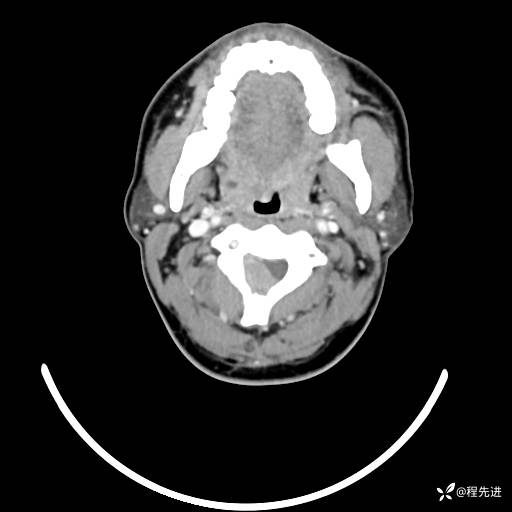

CT平扫+增强: